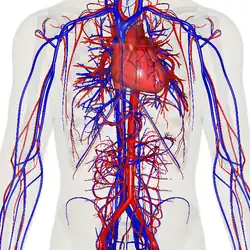

Кровеносная система человека. Красным обозначены артерии, синим — вены. Капиляры соединяют артерии с венами. | |

Циркулято́рная система, также система кровообращения и кровеносная система[1] — система органов, включающая сердце, кровеносные сосуды и кровь, которая циркулирует по всему телу человека или другого позвоночного[2][3]. Включает в себя сердечно-сосудистую систему (также кардио-васкулярная система от греческого kardia — сердце, и латинского vascula — сосуды), которая состоит из сердца и кровеносных сосудов. Кровеносная система состоит из большого и малого круга кровообращения[4].

Сеть кровеносных сосудов составляют магистральные сосуды сердца, включающие крупные артерии и вены, другие артерии и артериолы, а также капилляры, впадающие в венулы (мелкие вены), и другие вены. Кровеносная система у позвоночных замкнута, это значит, что кровь никогда не покидает сеть кровеносных сосудов. Некоторые беспозвоночные, такие как членистоногие, имеют открытую систему кровообращения. У диплобластов, таких как губки и гребневики, кровеносная система отсутствует.

Система кровообращения включает сердце, кровеносные сосуды и кровь[3]. Сердечно-сосудистая система у всех позвоночных состоит из сердца и сосудов. Кровеносная система делится на два основных контура — малый и большой круги кровообращения[2][4]. Малый круг кровообращения представляет собой контурную петлю от правого желудочка, по которой кровь поступает в легкие, где она насыщается кислородом и возвращается в левый желудочек. Большой круг кровообращения доставляет насыщенную кислородом кровь от левого желудочка к остальной части тела и возвращает кровь обратно в правый желудочек через крупные вены, известные как полые вены. Циркуляцию крови также можно разделить на две части — макроциркуляцию и микроциркуляцию. В среднем у взрослого человека содержится от пяти до шести литров крови, что составляет примерно 7 % от общей массы тела[9]. Кровь состоит из плазмы, эритроцитов, лейкоцитов и тромбоцитов . Пищеварительная система также работает совместно с системой кровообращения, обеспечивая организм питательными веществами, необходимыми для поддержания работы сердца[10].